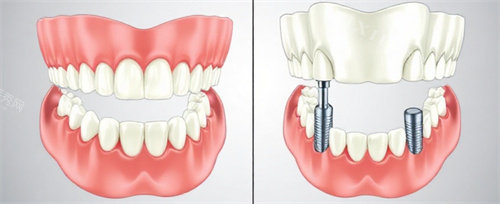

一、种植牙价格参考

(含CBCT+种植体+基台+金属冠,质保5-10年)

即刻负重/全口半口种植:现场评估后一口价,单颗再减200-400元。